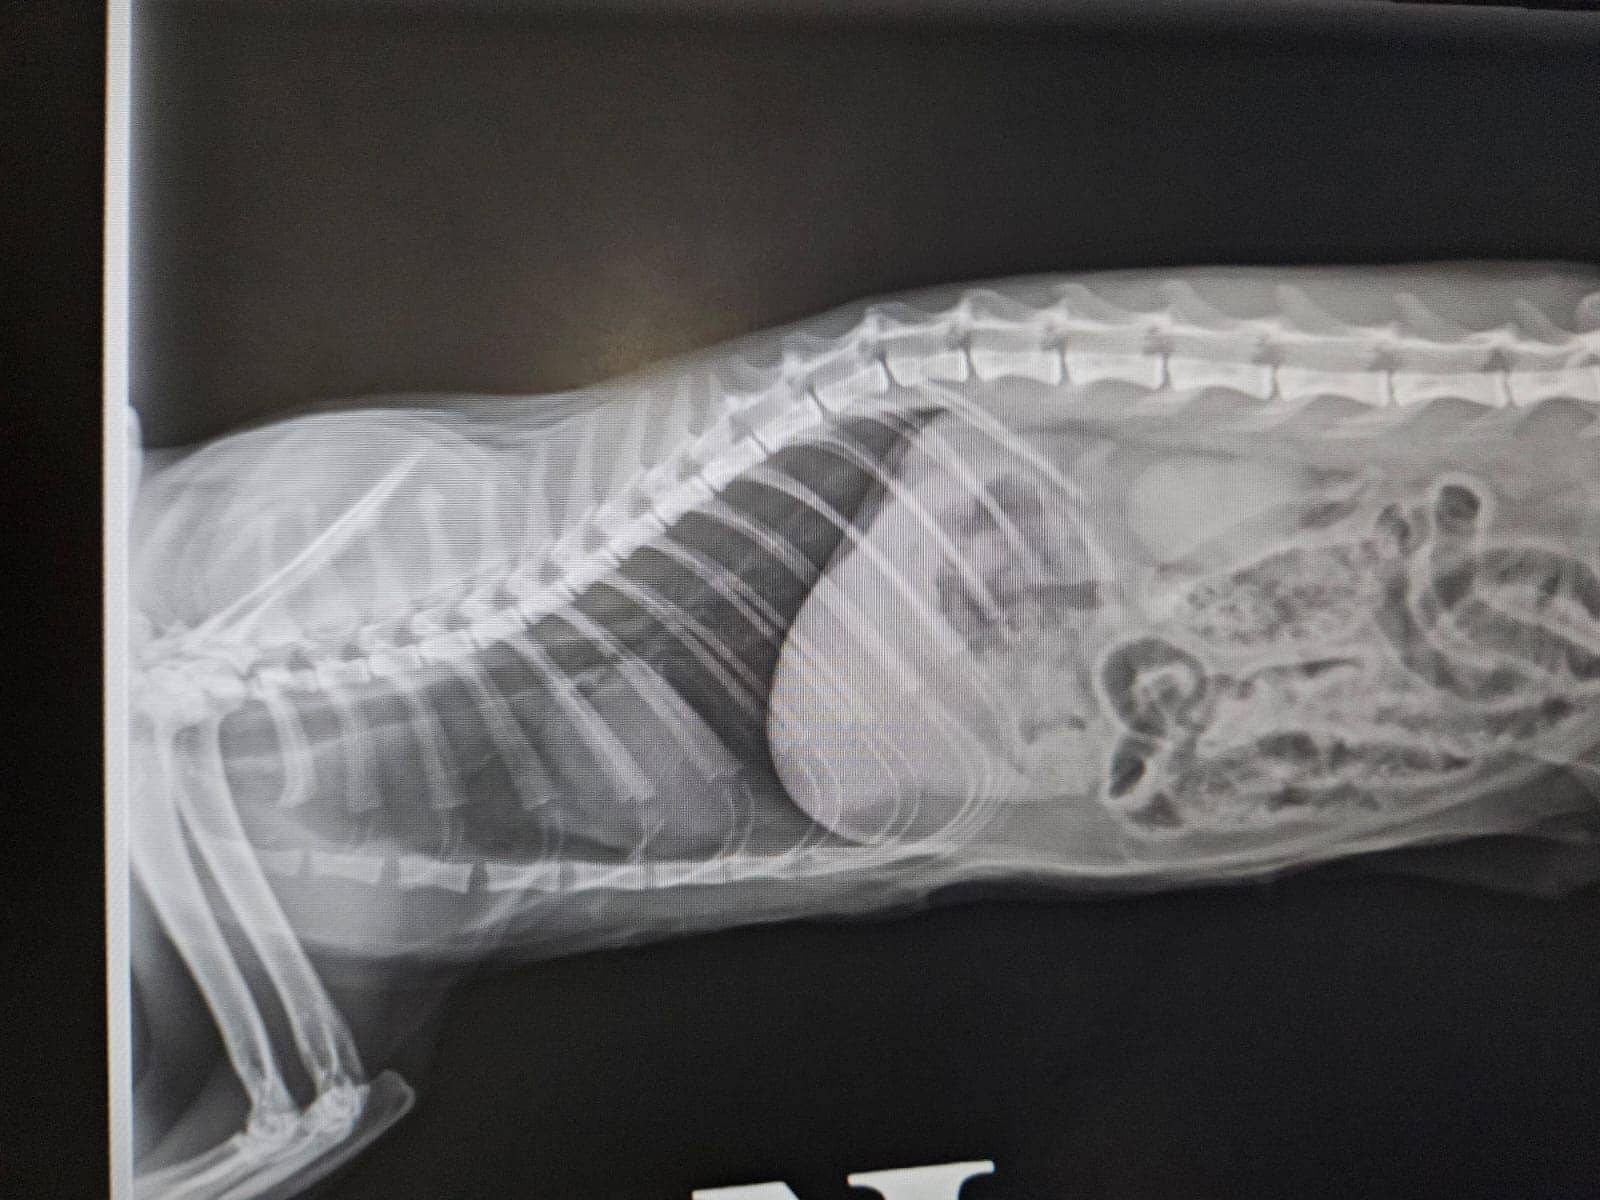

社交平台專頁毛守救援表示,昨晚(10月10日)九時半左右,有唐貓在錦田石崗菜站被一輛白色私家車撞到。受重傷唐貓為貓女,已經絕育及剪耳,頸有蝨帶。貓咪受傷後倒在馬路上,口鼻吐血,大腿有傷口及呼吸急速,情況嚴重,義工到場送院搶救24小時診所搶救。據影片所見,貓咪表情甚痛苦,地上亦留下大量血跡。